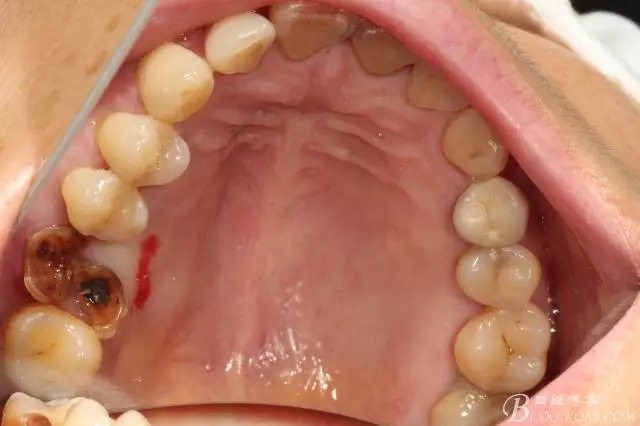

先26號牙位拔牙前照片顯示牙根頰舌向已經(jīng)裂開